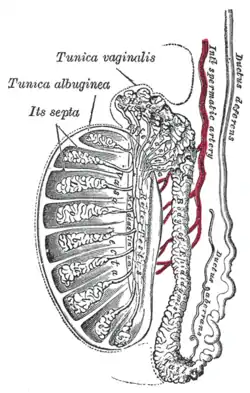

Vertical section of the testis, to show the arrangement of the ducts.

Vertical section of the testis, to show the arrangement of the ducts. Micrograph of the rete testis involved by seminoma. H&E stain.